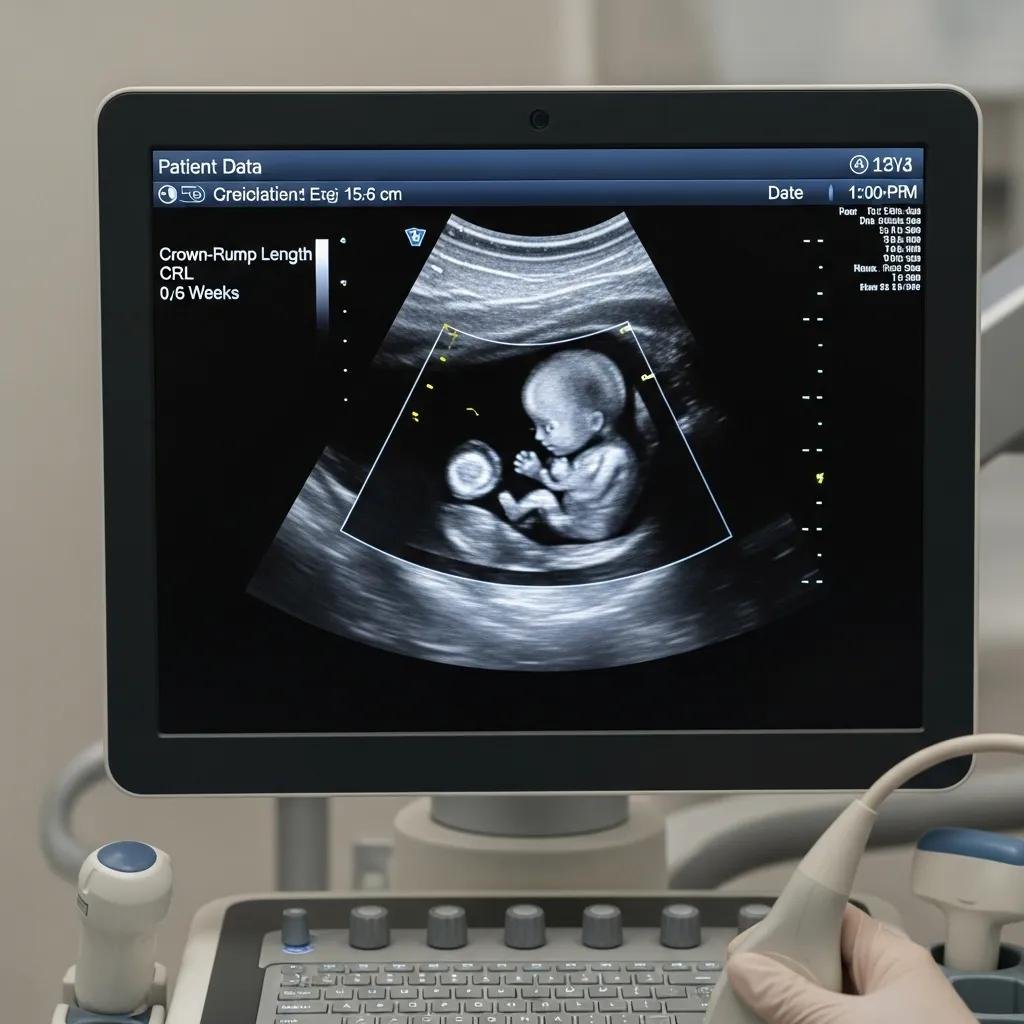

An early pregnancy scan (up to 12 weeks gestation) (also called a viability scan or first trimester scan) is an ultrasound examination performed between 6 and 14 weeks of pregnancy. It is used to confirm that a pregnancy is developing normally inside the uterus, to check for a heartbeat, and to give an accurate gestational age based on the size of the embryo or fetus.

The scan can be performed either transabdominally (through the lower abdomen) or transvaginally (with a small probe placed in the vagina). The transvaginal approach gives a clearer image in early pregnancy, particularly before 8 weeks, when the embryo is very small. Both methods are safe and well-tolerated, and Dr Mermigka will explain each step before proceeding.

- Pelvic ultrasound scan — transabdominal or transvaginal as clinically appropriate. The screen is positioned so you can see the images.

- Discussion of findings — Dr Mermigka explains what is visible, the gestational age, and the heartbeat if present.